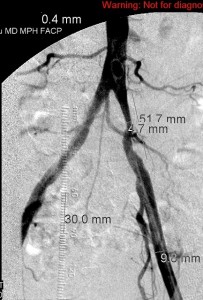

The images below illustrate percutaneous stenting of stenosis of the distal proximal and the mid left common iliac artery, without disease of the left external iliac artery in one of my patients who presented with left calf claudication. CTA of his abdominal aorta and arterial duplex ultrasound of his lower limbs ( images not shown) revealed left iliac stenosis, confirmed by the digital subtraction angiographic images in the first row. He did well following stenting of the diseased artery. Iliac arterial stenting stays open for nearly as long as surgical revascularization and at much less the morbidity and cost of the latter.